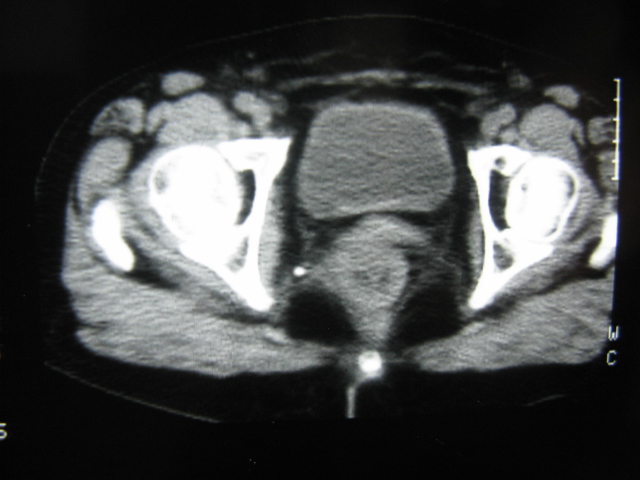

患者,女,64岁,2002年诊断为宫颈癌,当时只做过放,化疗。现在诊断:(1)宫颈癌。(2)直肠癌。请同道们讨论,探讨。另外肠壁为啥密度这么高,ct值约112hu。患者没有做过增强和造影。

高密度的不是肠管影,是肠管内的粪便影

患者直肠病变,排便不畅,粪便硬结造成,更高密度如钡灌肠者都可出现

硬结粪便能有如此高密度影?

我也碰到过几例,最离奇的一例是全结肠呈造影样高密度,患者直肠癌(首次发现),以往没有吃药,只有约半年时间长的胃纳差,排便不畅(据患者说每次大便只能拉出少许黄水)

不一定有意义,可清洁灌肠后复查